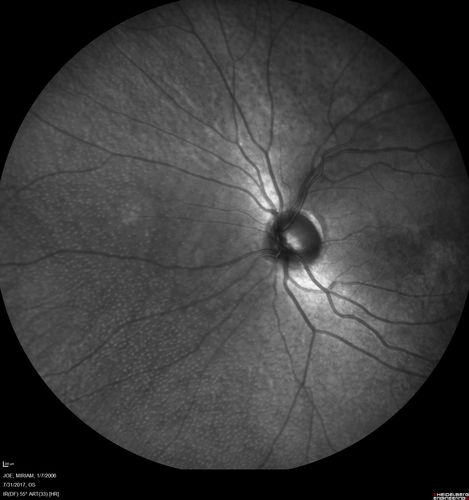

Fundus Albipunctatus

12 year old female with normal vision. She has 4 siblings all of whom have either white spots or spots on IR. Genetic testing by parents was deferred.